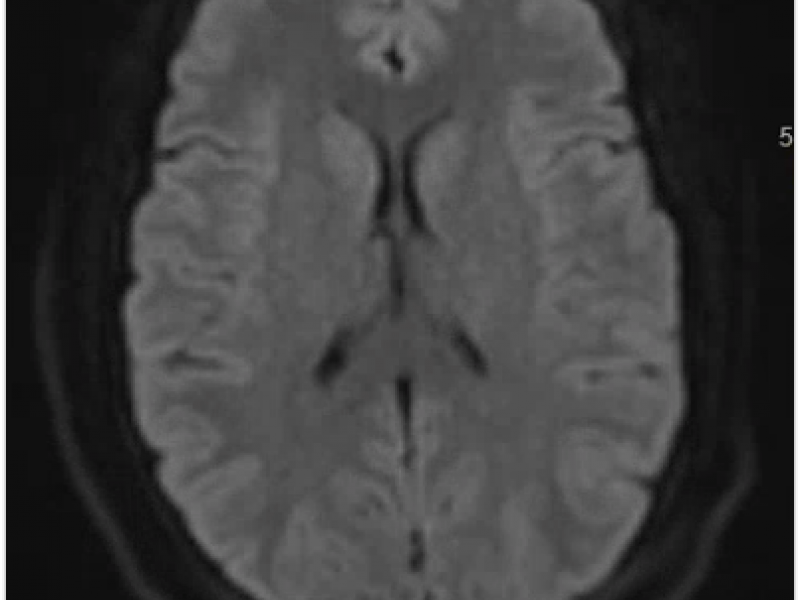

HPI 24 yo female hx of gradual onset severe frontal